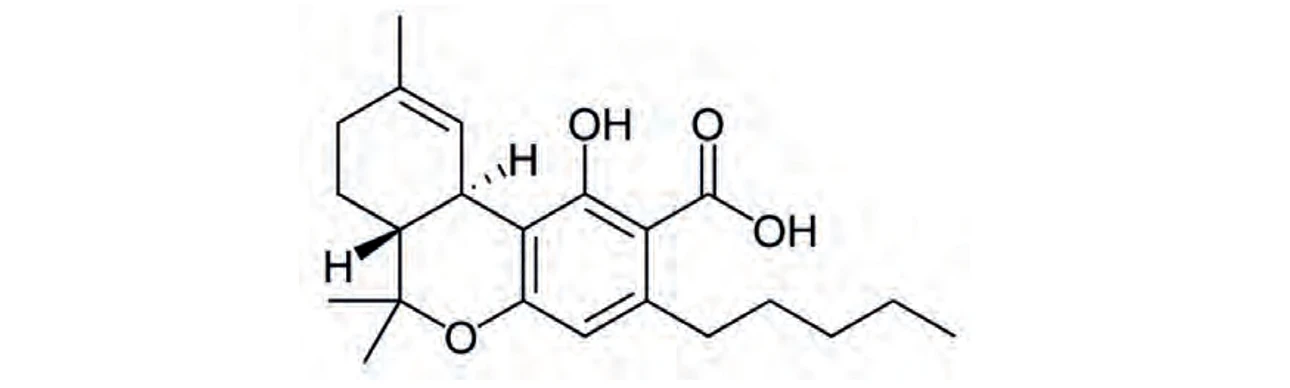

PČR: Kyselina Δ9-trans-tetrahydrokanabinolová (THCA) – její oxidací vzniká THC (16)

PČR: Kyselina Δ9-trans-tetrahydrokanabinolová (THCA) – její oxidací vzniká THC (16)

PČR: Kyselina kanabidiolová (CBDA)

PČR: Kyselina kanabidiolová (CBDA)

PČR: Kyselina kanabigerolová (CBGA)

PČR: Kyselina kanabigerolová (CBGA)

Biosyntéza (Obr. 5) začíná vytvořením dvou kanabinoidních prekurzorů – geranyldifosfátu a olivetové kyseliny, které spolu kondenzují za účasti geranyltransferasy a vzniku kanabigerolové kyseliny (CBGA). CBGA se následně transformuje na tetrahydrokanabinolovou kyselinu (THCA), kanabidiolovou kyselinu (CBDA) a kanabichromenovou kyselinu (CBCA) pomocí THCA synthasy, CBDA synthasy a CBCA synthasy. Tetrahydrokanabinol (THC), kanabidiol (CBD), kanabigerol (CBG) a kanabichromen (CBC) vznikají dekarboxylací ze svých kyselin během skladování vlivem tepla a světla za uvolnění CO211. THC a iso-THC mohou také vznikat kysele katalyzovanou cyklizací CBD vytvořením příslušných karbokationtů na C-8 a C-1 CBD skeletu (25).

PČR: Obr. 5 – Biosyntéza kanabinoidů a hlavní rozkladné produkty THC (8)

PČR: Obr. 5 – Biosyntéza kanabinoidů a hlavní rozkladné produkty THC (8)